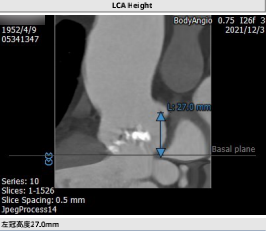

主动脉瓣影像分析:

李妍主任提出该患者为TYPE 0型二叶瓣,重度钙化,主要分布于瓣叶交界,升主动脉较宽,窦部结构大,双侧股动脉入路均有钙化,术中注意轻柔操作,同时主动脉弓部大折角,大弯侧钙化侧瓣叶钙化重,可能存在输送系统过弓困难及跨瓣困难及瓣膜下滑风险术中密切注意,逐决定抓捕器辅助,24球囊预扩,选择植入VitaFlow Liberty ™30瓣膜,根据术中瓣膜形态及有无瓣周漏,做后扩准备。手术投照角度选取右窦最低,LAO结合CRA体位,保证看到窦底最底点,提高定位精度。